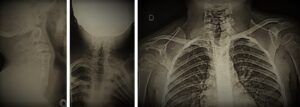

Diagnostic imaging examples of Klippel-Feil Syndrome and Sprengel Deformity, differing views.

Sprengel deformity is commonly associated with Klippel-Feil Syndrome, and is a rare congenital disorder in which the scapula is too high on one side of the body. The main signs and symptoms of Sprengel deformity are limited or restricted movement of the arm and shoulder blade, as well as the cervical spine. Some individuals may present with neck deformities as well, ranging from torticollis to severe spine deformity. CT scans and MRI are commonly used to confirm a diagnosis of Sprengel deformity.